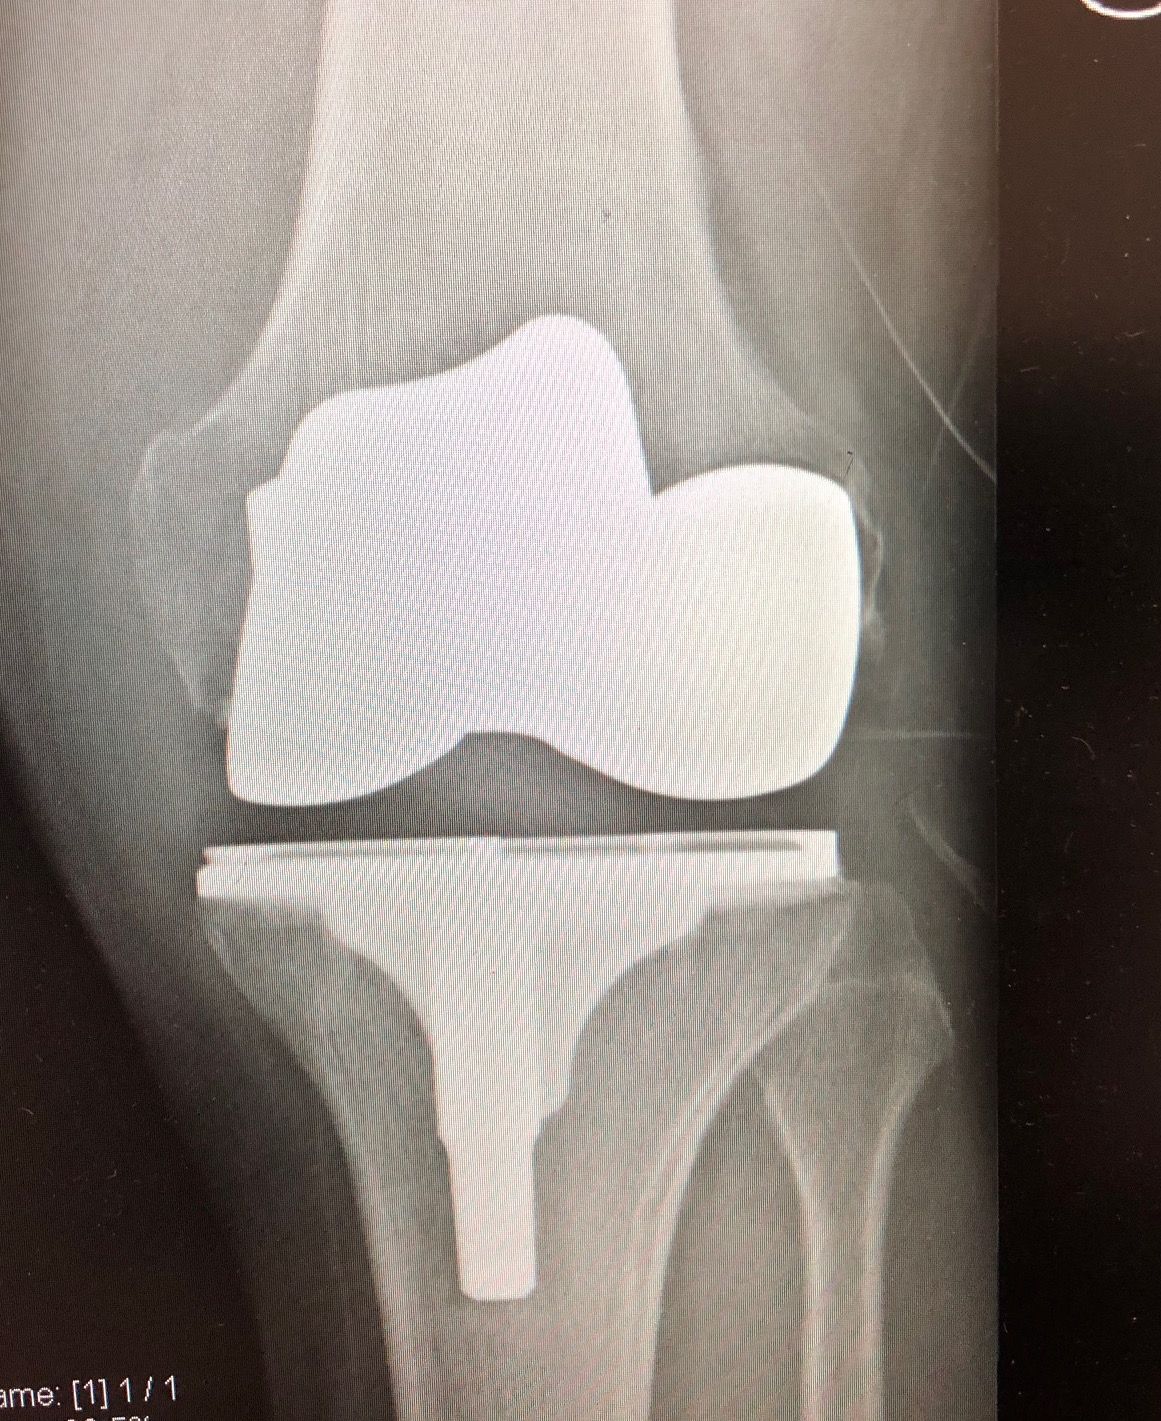

Sono specializzato nell'impianto di protesi di ginocchio ed anca in caso di patologie degenerative artritiche o necrotiche. Utilizzo protesi di ultima generazione, le protesi di ginocchio vengono applicate utilizzando una maschera creata su misura per ogni paziente, quelle di anca sono studiate per ridurre al minimo il rischio di lussazione (principale complicazione di questo tipo di intervento).

Foto e video

Salve, ho 54 anni e a giugno del 2019 ho fatto l'artoprotesi completa del ginocchio destro. Al controllo annuale ho fatto l'RX sotto carico in due proiezioni il cui referto è : "Protesi bicompartimentale apparentemente ben posizionata ed impiantata. Entesite calcifica del tendine quadricipitale".

Vorrei sapere se l'entesite si potrebbe risolvere in maniera spontanea o se è neccessario intervenire e come?